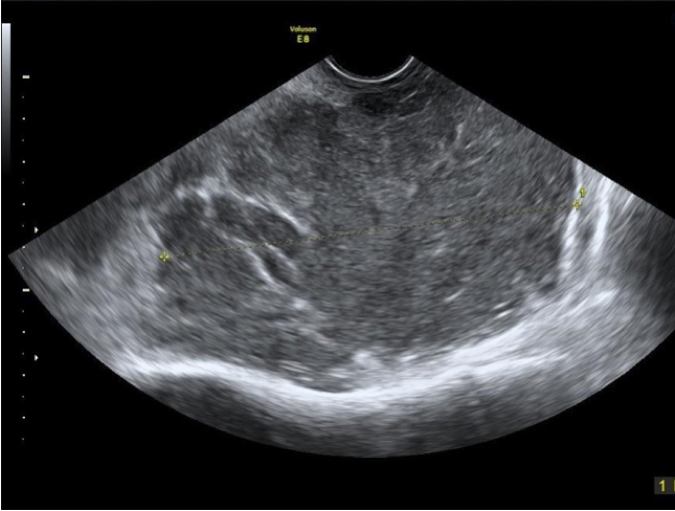

Granulosacellstumörer producerar ofta östrogen och förekommer hos kvinnor i alla åldrar. I en serie på 23 fall beskrivs tumören som ensidig, solid eller flerrummigt solid (många gånger solid med små cystiska hålrum, s.k. ”schweizerost”). Den har rikligt blodflöde och oregelbunden ekogenicitet med en medeldiameter på 10 cm3. Se bild 5.

Bild 5. Granulosacellstumör hos 30-årig kvinna med blödningsrubbningar och infertilitet.